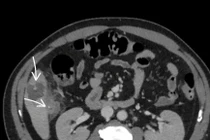

Kết quả nội soi dạ dày cho thấy: Sát môn vị có hình ảnh mảnh xương dài khoảng 3cm cắm vào thành dạ dày, vùng xung quanh phù nề, xung huyết nhiều và có loét. Khai thác tiền sử bệnh nhân cho biết, cách ngày vào viện 4 ngày bệnh nhân có ăn cháo gà, sau đó chỉ đau bụng âm ỉ nên chủ quan không đi khám.

manh-xuong-ga.jpg

Mảnh xương đâm xuyên dạ dày tạo ổ áp xe